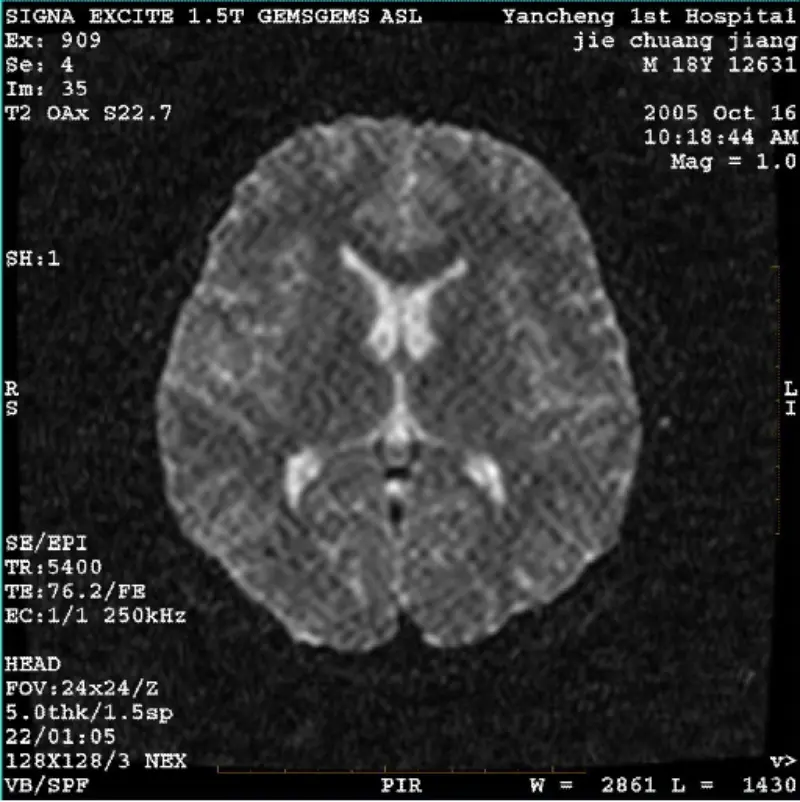

View DetailsSYSTEM: 1.5T Signa Twin Excite II (Software Version 11.0M4) PROBLEM/SYMPTO DWI (Zoom mode and whole mode) and fiesta (zoom mode and whole mode) image having visible reticulate or corduroy artifact no matter when using body coil or head coil, other routine image seems normal